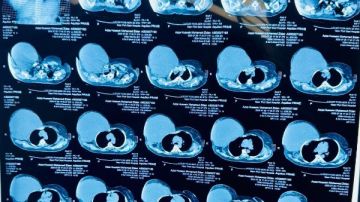

أعلنت الهيئة العامة للرعاية الصحية، برئاسة الدكتور أحمد السبكي، رئيس الهيئة والمشرف العام على مشروع التأمين الصحي الشامل، عن نجاح فريق طبي بمستشفى السلام ببورسعيد – أحد مستشفيات الهيئة – في إجراء عملية جراحية دقيقة ونادرة لسيدة خمسينية، تضمنت استئصال ورم ضخم يزن ستة كيلوجرامات من جدار الصدر الأمامي مع إعادة بنائه.

هذا، وتعود تفاصيل الحالة إلى استقبال مستشفى السلام ببورسعيد لسيدة تبلغ من العمر خمسًا وخمسين عامًا كانت تعاني من ورم ضخم في جدار الصدر بلغ حجمه أربعين في ثلاثين سنتيمترًا واستمر أكثر من ثمانية أشهر بعد رحلة طويلة من المعاناة تنقلت خلالها بين عدد من المستشفيات دون جدوى، وبمجرد دخولها المستشفى بادر الفريق الطبي بوضع خطة علاجية متكاملة انتهت بإجراء العملية بنجاح كامل واستئصال الورم مع إعادة بناء القفص الصدري باستخدام أحدث التقنيات الطبية، وقد استغرقت العملية عدة ساعات متواصلة بمشاركة فريق طبي متعدد التخصصات في جراحة الأورام والجراحة العامة وجراحة التجميل والتخدير والعناية المركزة.

وخرجت المريضة من المستشفى بعد أربعة أيام فقط من المتابعة الدقيقة بالعناية المركزة وهي في حالة صحية مستقرة، وتخضع حاليًا لبرنامج متابعة مستمر للاطمئنان على حالتها وضمان تعافيها الكامل، ويُعد هذا التدخل من العمليات النادرة والمعقدة نظرًا لضخامة الورم وموقعه الحساس.